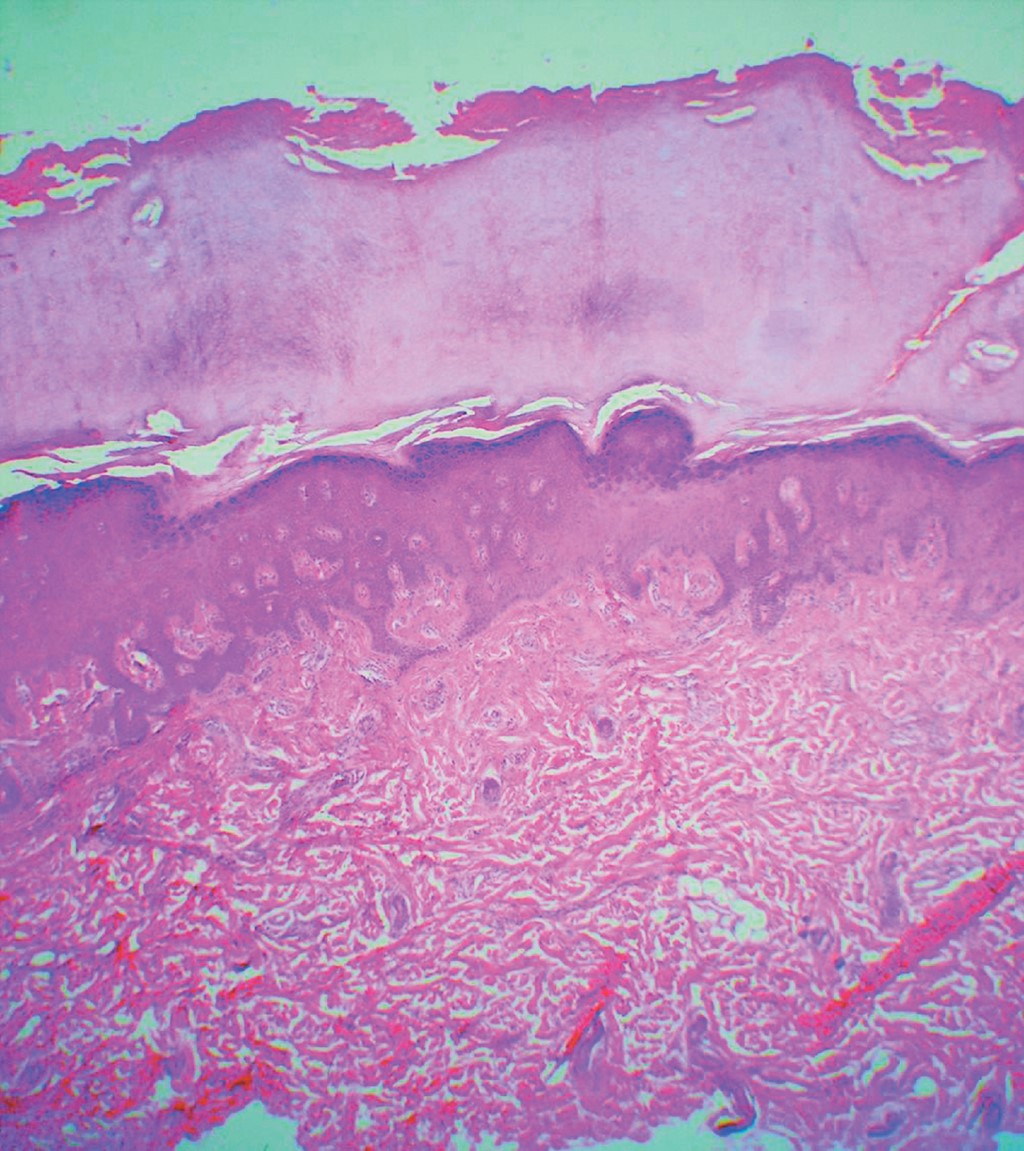

Hereditary palmoplantar keratoderma Wachters type. Communication of a case

Palmoplantar keratodermas are a heterogeneous group of diseases, characterized by marked thickening of the epidermis on the palms and soles. They may have an acquired or hereditary origin, and according to their distribution they can be, diffused, localized (nummular/ linear) or papular. In this article we present the case of a patient with Wachters' palmoplantar keratoderma, with a probable autosomic recessive inheritance, that presented keratotic localized painful plaques on palms and feet, without association to another disease.

Figure 2